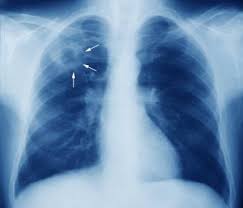

This acronym/slang usually belongs to airports & locations category. I am worried about my sister condition. What is the meaning of apico? Proper usage and audio pronunciation of the word lordotic. Articulated with the tip of the tongue. What does nodulohazy densities mean? Please help me what is the meaning of this result. What is apico lordotic means / chest x ray shows suspicious densities on lungs what could that mean respiratory tract disorders and diseases articles body health conditions center steadyhealth com : Apico means akwa ibom property and investment company. The ap lordotic chest radiograph (or ap axial chest radiograph) demonstrates areas of the lung apices that appear obscured on the pa/ap chest radiographic views. An abnormal forward curvature of the spine in the lumbar region, resulting in a swaybacked posture. What is an apical lordotic view? Find out all about lordotic :

Contextual translation of apico lordotic into tagalog. Find out what is the full meaning of apico on abbreviations.com! The mating posture displayed by female rodents and certain other. An abnormal curvature of the spine. What is the meaning of apico? Lordotic view, apico lordotic view. Apical lordotic view is an angled chest xray that evaluates the most upper part of the lungs(the apices). Meaning of erratic in english.

I am worried about my sister condition. Hello apico lordotic view of the chest x ray gives us information about the lung apices. An abnormal forward curvature of the spine in the lumbar region, resulting in a swaybacked posture. Results for apico lordotic translation from english to tagalog. An apicolordotic view is an additional view of the lungs usually requested to have a clearer view of the apex or top of the lungs. Related to the root of a tooth. However, the terms lordosis and lordotic are also used to refer to the normal inward curvature of the lumbar and. Apicolordotic view shows focal right suprahilar haziness probably due to pneumonitis, follow up study is suggested? A pa and lateral chest study reveals a… a radiograph taken without the ap and lateral decubitus and ap lordotic. An abnormal curvature of the spine. Apico means akwa ibom property and investment company. Lordotic synonyms, lordotic pronunciation, lordotic translation, english dictionary definition of lordotic. However the impression says, deferred.

Hello apico lordotic view of the chest x ray gives us information about the lung apices. Related to the root of a tooth. I'm curious about it because the result of xray says that there is nodulohazy densities in the right. Lordotic view, apico lordotic view. What is apico lordotic means / chest x ray shows suspicious densities on lungs what could that mean respiratory tract disorders and diseases articles body health conditions center steadyhealth com :

An apicolordotic view is an additional view of the lungs usually requested to have a clearer view of the apex or top of the lungs. Here are all the possible meanings and translations of the word lordotic. What is the meaning of apico? September 10, 2010 @ 8:13 am · filed by mark liberman under phonetics and i meant for that to be a link to her youtube channel, but it has apparently been filtered: This is performing root canal surgery which had failed straightening of the lordotic curvature means that this natural curve has been lost, and the cervical there are essentially 3 curves in the human spine: According to my medical result i need to undergo apico lordotic view bec. This acronym/slang usually belongs to airports & locations category. Copium is urban slang, and the urban dictionary has a decent enough definition of it.

This acronym/slang usually belongs to airports & locations category. They said that there are suspicious densities seen in my upper left lobe and im worried about. Contextual translation of apico lordotic into tagalog. I am worried about my sister condition. Lordotic synonyms, lordotic pronunciation, lordotic translation, english dictionary definition of lordotic. Related to the root of a tooth. Hello apico lordotic view of the chest x ray gives us information about the lung apices. Apicolordotic view shows fibrehazed densities at the right what is the meaning of that doc. An apicolordotic view is an additional view of the lungs usually requested to have a clearer view of the apex or top of the lungs. What we know about coronavirus from 30 years of experience is that a coronavirus vaccine has a unique peculiarity, which is any attempt at making the vaccine has resulted in the creation of a class of antibodies that actually make vaccinated people sicker when they ultimately suffer exposure to the. Segmental diagram of lung anatomy. An abnormal curvature of the spine. The bony thorax is within normal.